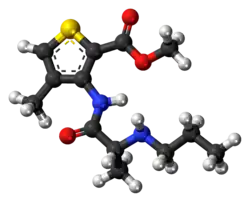

Lokalanästhetika liegen chemisch in zwei Formen vor. Während die nicht dissoziierte, lipophile Base zum Nerv vordringt, ist die hydrophile, dissoziierte Form (Kation) lokal wirksam. Sie blockiert den Natriumeinstrom in (Nerven-)Zellen und somit die Reizleitung. Je dicker die Nervenfaser, desto höher muss die Konzentration des Lokalanästhetikums sein. Aufgrund des geringen Durchmessers der schmerzleitenden C- und A-delta-Fasern werden diese früh gehemmt, während die motorischen A-alpha-Fasern erst spät unterbunden werden.[4]

Nachdem der Augenarzt Carl Koller (1857–1944) 1884 erkannte, dass Kokain bei Verkostung die Zunge betäubt,[89] benutzte 1885 der Chirurg William Stewart Halsted (1852–1922) erstmals Kokain in der Zahnmedizin. Nach ersten Tierversuchen wendete er das Verfahren zur Betäubung des Nervus mandibularis als Leitungsanästhesie an. Neben der Oberflächen- und Leitungsanästhesie entwickelte sich daraus die Infiltrationsanästhesie. 1905 verlängerte der Leipziger Chirurg Heinrich Braun die Wirkdauer und -tiefe des von Alfred Einhorn entwickelten Procains, welcher dem Wirkstoff den Namen Novocain zuordnete, durch die Beigabe von Adrenalin. Dem aus Heilbronn stammenden Chemiker Friedrich Stolz war es 1905 im Auftrag von Hoechst gelungen, das Hormon Suprarenin künstlich herzustellen. Der Zahnarzt und Anatom Harry Sicher beschrieb 1920 in seinem Lehrbuch „Anatomie und Technik der Leitungsanästhesie im Bereiche der Mundhöhle“ die exakte Vorgehensweise bei der Durchführung der verschiedenen Lokalanästhesien im Mundbereich.[90] Lidocain war das erste Amino-Amid-Lokalanästhetikum, das durch die schwedischen Chemiker Nils Löfgren (1913–1967) und Bengt Lundqvist (1922–1953) im Jahre 1943 synthetisiert wurde.[91] Sie verkauften die Patentrechte des Lidocains an den schwedischen Pharmakonzern Astra AB. 1957 schritt die Entwicklung der Lokalanästhetika mit Synthetisierung des Mepivacains, 1963 des Bupivacains, 1958 des Prilocains und 1976 des Articains voran.[92] Im Jahre 1981 wurde als neue Anästhesiemethode die intraligamentäre Anästhesie entwickelt. Erste Versuche gab es bereits 1920 in Frankreich, wo die „Anesthésie par injections intraligamenteuses“ berichtet wird. Sie konnte sich zum damaligen Zeitpunkt aufgrund der zur Verfügung stehenden Instrumente nicht als Standardmethode durchsetzen.[93]